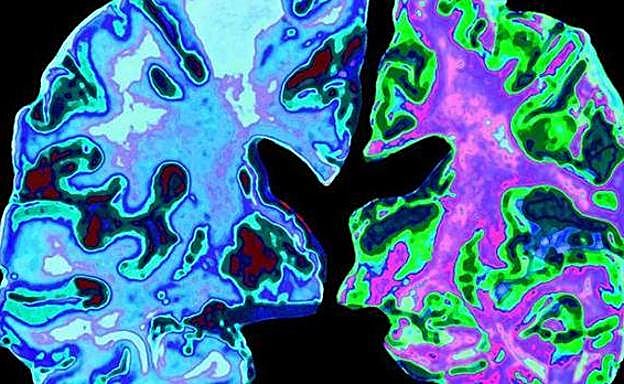

Late, la nueva demencia que se confunde con el alzhéimer

Los investigadores caracterizan una forma diferente de demencia denominada Late que progresa más gradualmente que el alzhéimer pero que, combinadas parecen causar un deterioro más rápido que cualquiera de las dos enfermedades por sí solas